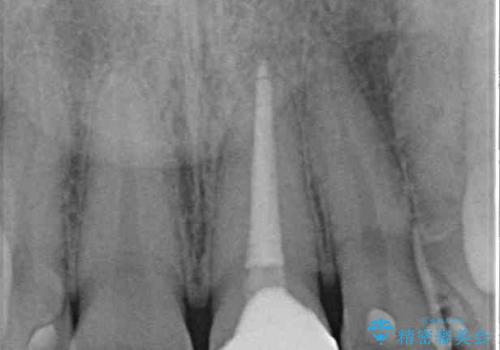

- 前歯の色を気にして来院された患者様です。

むし歯で神経が取り除かれており、歯の変色と充填材の変色などにより、つぎはぎのような前歯となっていました。

膿の出口も認められたため、まずは根管治療を実施し、オールセラミッククラウンにて補綴治療を行うこととしました。